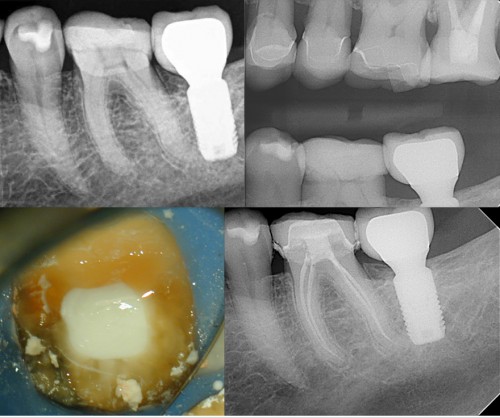

Lower Molar Treatment-IP prior to getting crown

This is a guitar player who was having a crown made, and developed pain to […]